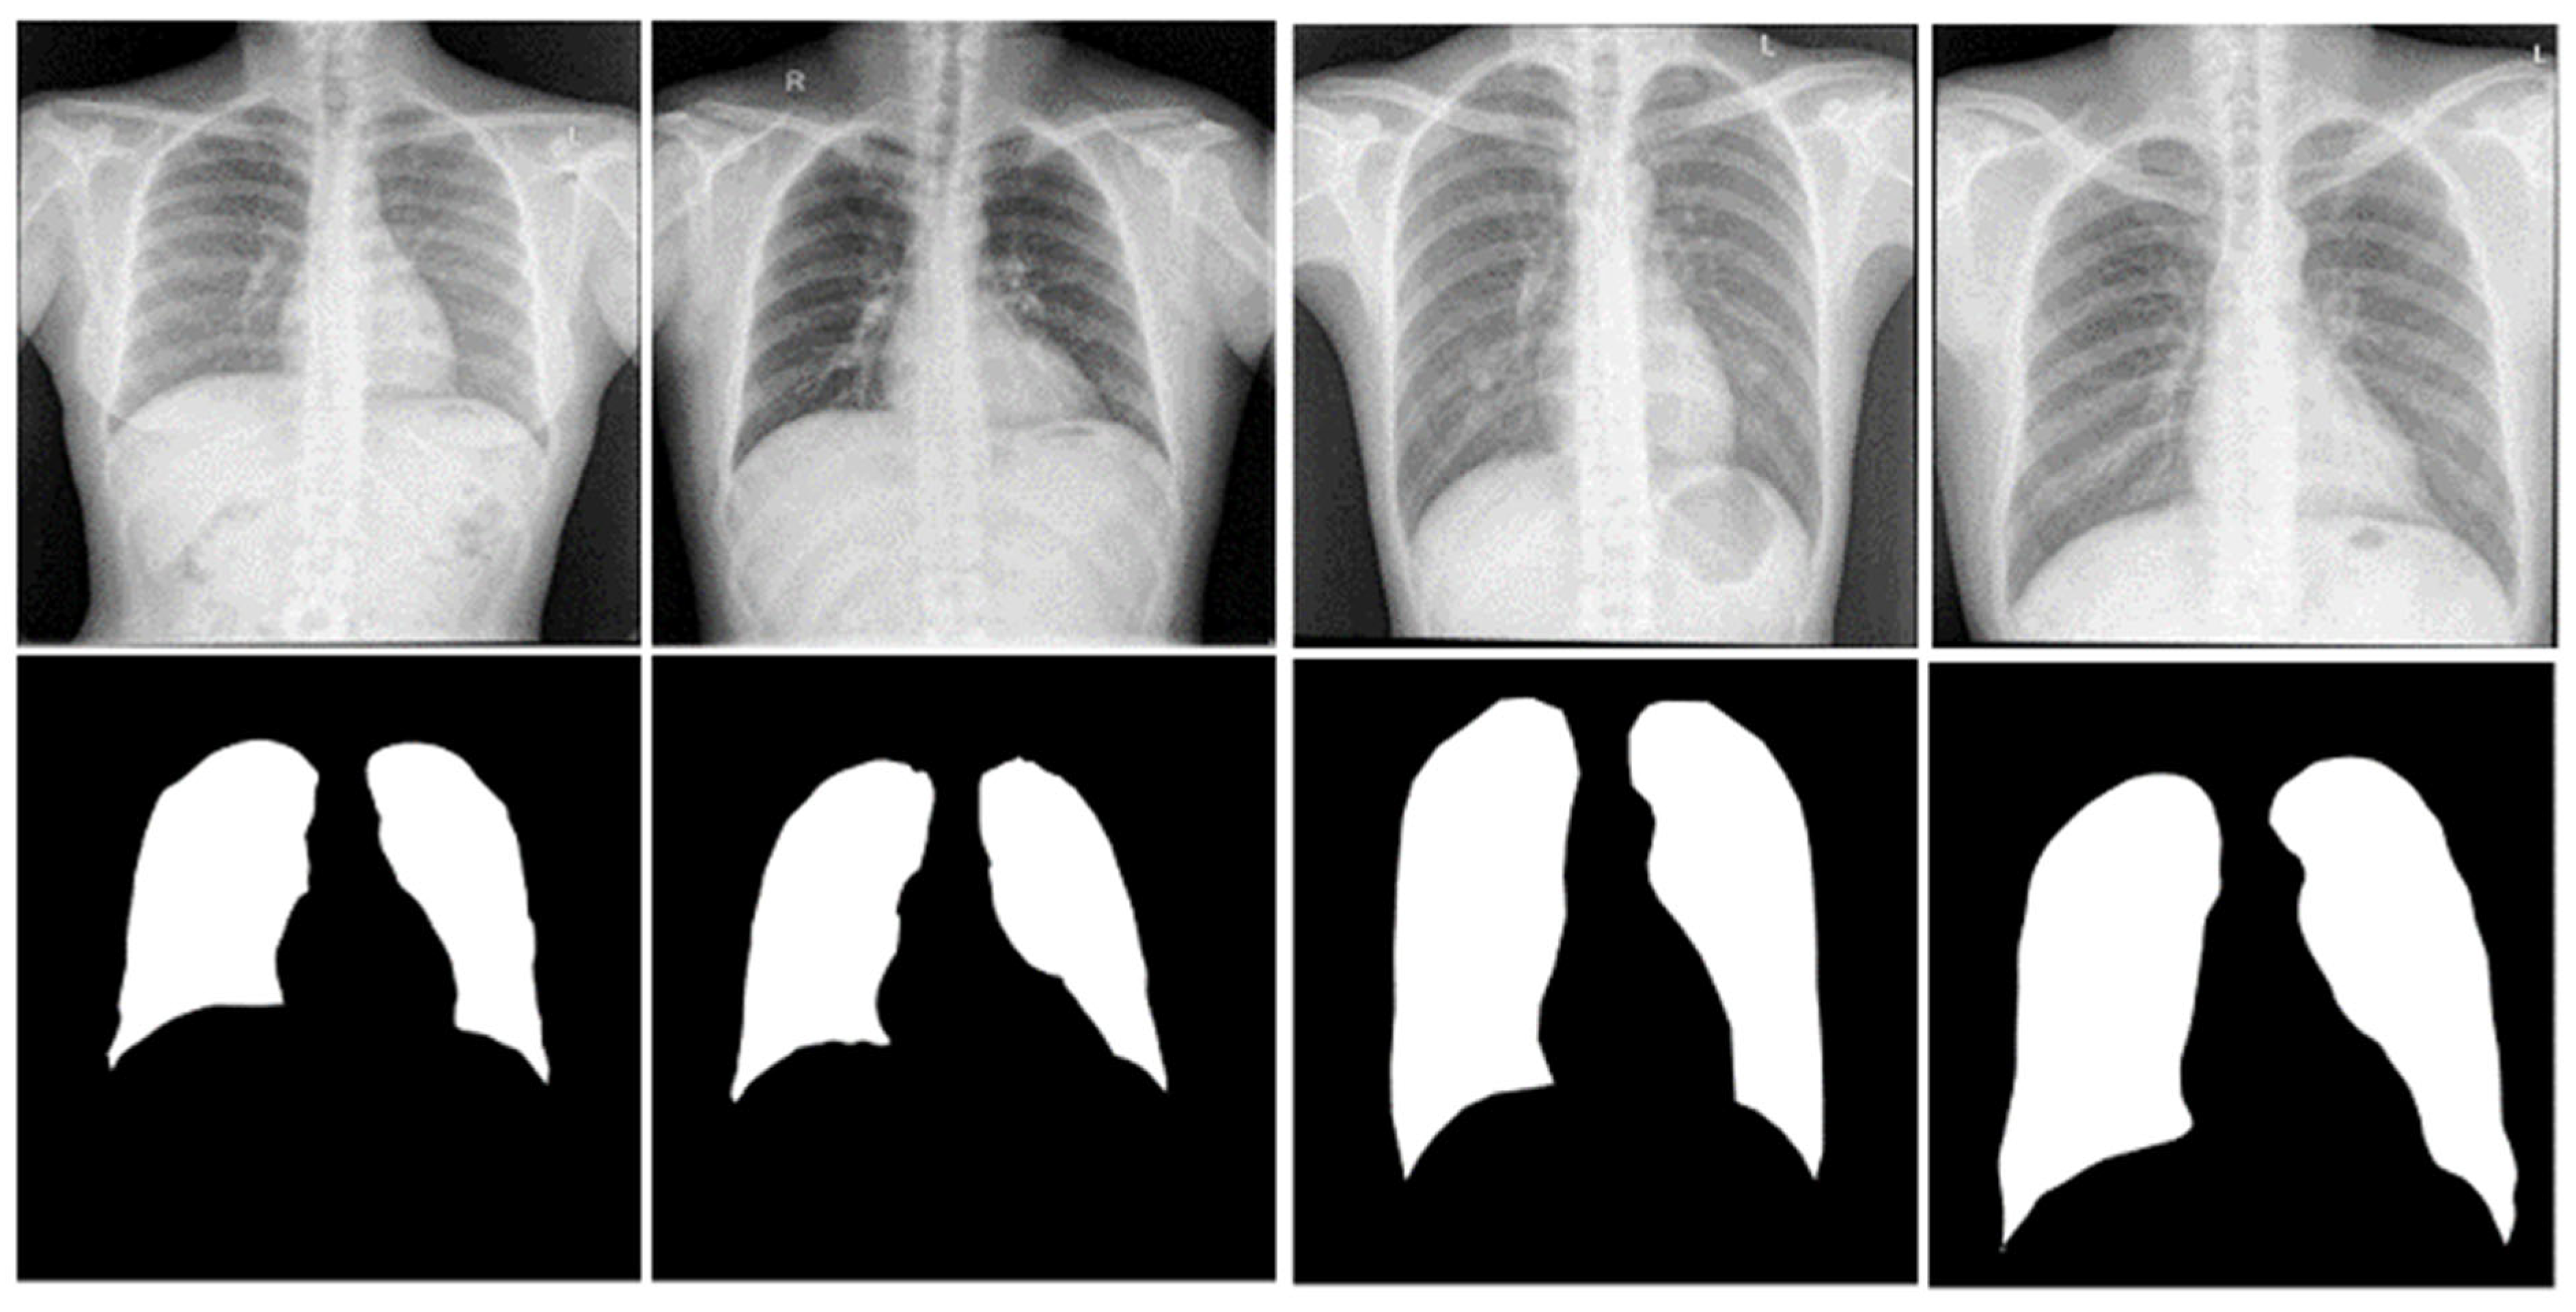

3.1. Segmentation

3.1.6. Segmentation of the Classification Dataset